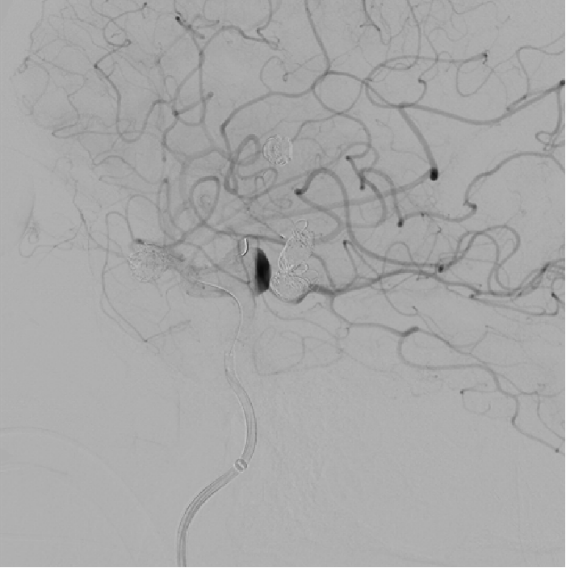

Preoperative angiography revealed a shared trunk of bilateral anterior cerebral arteries, with a saccular aneurysm (8 mm × 6 mm) on the left anterior cerebral artery, a recurrent aneurysm (9 mm × 5 mm) on the left middle cerebral artery, and a wide-neck aneurysm (8 mm × 8 mm) on the right posterior communicating artery.

Anterior-Posterior view of the left internal carotid artery

Post-treatment imaging of the left middle cerebral recurrent aneurysm and left anterior cerebral saccular aneurysm

Working position angiography of the right internal carotid artery